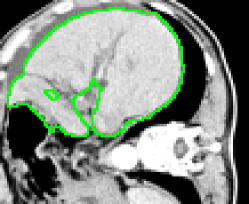

4.1 Metrication artifacts and minimal surfaces

We begin by comparing the CCMF segmentation result with the classical max-flow algorithm (graph cuts). Figure 3 shows the segmentation of a brain, in which the contours obtained by graph cuts are noticeably blocky in the areas of weak gradient, while the contours obtained by both AT-CMF and CCMF are smooth.